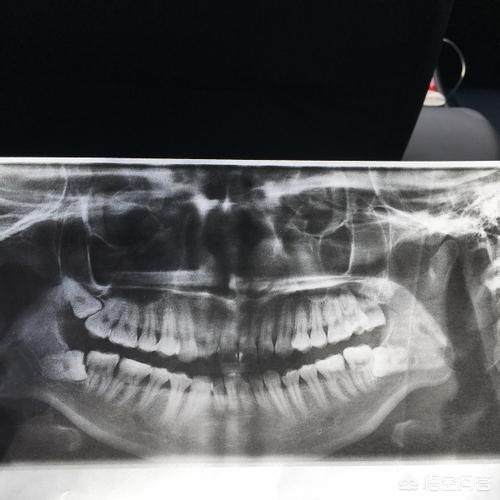

具体采用何种方式获取间隙则需要正畸医生通过X光片测量诊断后才能制定方案。

正畸是一个专业而复杂的过程,一个正确的治疗方案需要综合考虑多种因素,诸如畸形分类、正畸方法、患者年龄等等。